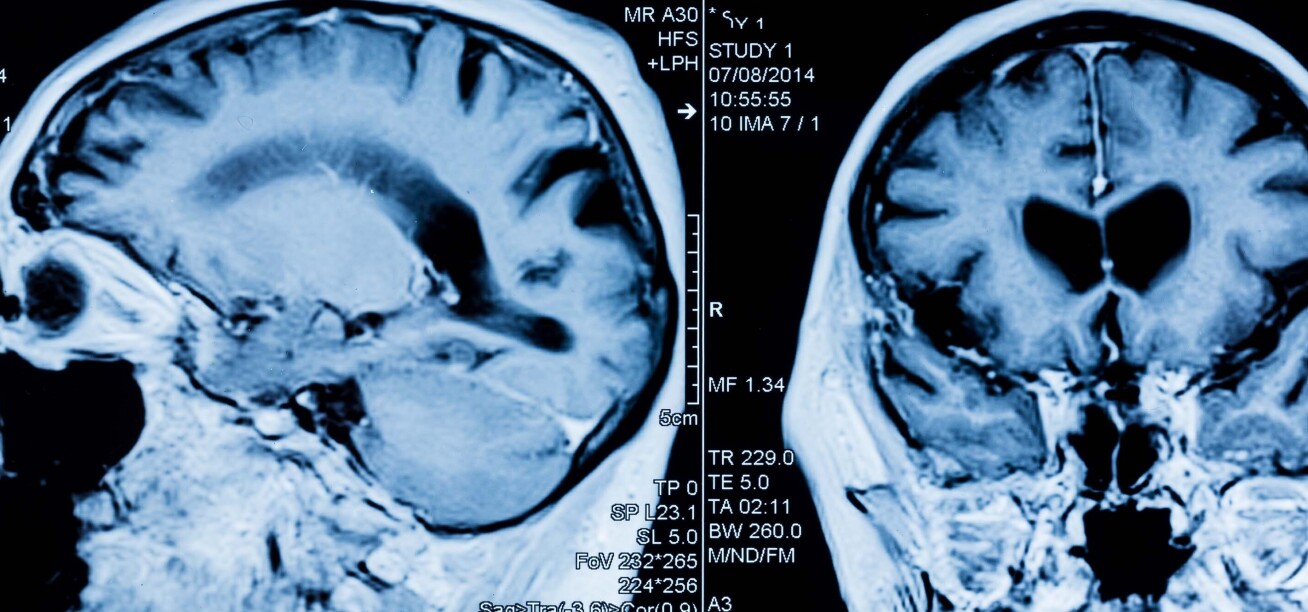

Brain changes in contact sport

Elite contact sports have an array of health benefits, but there are growing concerns that repeated knocks to the head could impact the long-term brain health of players.

New research has uncovered another piece of this complex picture, but the authors say the long-term impacts are still unclear.

Using data from a study pioneered and funded by The Drake Foundation, researchers in Imperial’s Department of Brain Sciences analysed brain scans of professional rugby players to look for any structural differences, compared to healthy controls of the same age.

They found that elite rugby players had evidence of changes in the cortical grey matter (the outermost layer of the brain) related to both long term rugby participation and recent head injury.

The researchers explain while the analysis shows physical changes linked to head injury, any potential long-term impacts on players’ brain health and function are still unknown. They add that the work highlights the importance of continued research in this area.

Read the full paper in the journal Brain Communications.